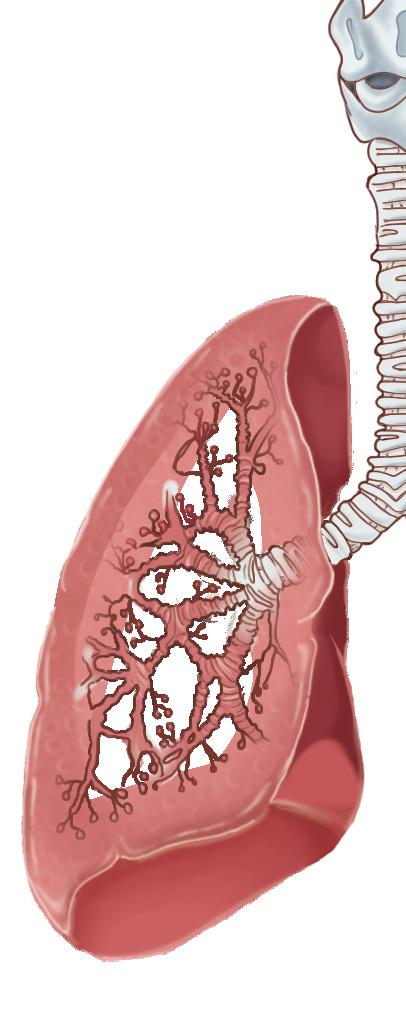

Concerns regarding the public health impacts of Hamilton’s air quality continue to persist despite efforts to improve air pollution in the region in the last 20 years.11 The 2011 Air Quality Health Assessment Study estimates that air pollutants, including nitrogen dioxide (NO₂), ground-level ozone (O₃), PM₁₀, fine respirable particulate matter (PM₂.₅), SO₂, and carbon monoxide (CO) are associated with 186 premature deaths, 395 respiratory hospital admissions, and 322 cardiovascular hospital admissions annually in Hamilton.12

Adverse health effects associated with particulate pollution from the Hamilton industrial sector is not a new issue. In 1984, Pengelly et al. conducted a cohort study assessing the respiratory health of 3,553 children aged seven to ten years living in different quadrants of the Hamilton region corresponding with varying levels of air pollution, represented by total suspended particulate (TSP) measurements.13 Children living in the industrial core experienced the highest prevalence of respiratory hospital admission in infancy, reinforced with confounders such as the highest prevalence of parental cough, chest illness in siblings, low income, smoking in the home, and crowding in the house.13 The industrial core area is also associated with the highest ambient pollution levels, with an average annual TSP measurement of 93 μg/m3, much greater than the current 60 μg/m³ annual TSP standard set by the Ontario AAQC.13,14 The upper city areas generally had a lower prevalence of these covariables and respiratory hospitalizations, corresponding

with lower levels of TSP air pollution.13 Particulate matter, including PM₂ ₅ and PM₁₀, may be inhaled and deposited throughout the airways, inducing pulmonary inflammation and oxidative stress through reactive oxygen species (ROS) generation.15,16 ROS damage cells and tissues due to the susceptibility of structural proteins, enzymes, and DNA to oxidation, which is especially problematic in airway epithelium as it is the first line of defense against inhaled oxidants.